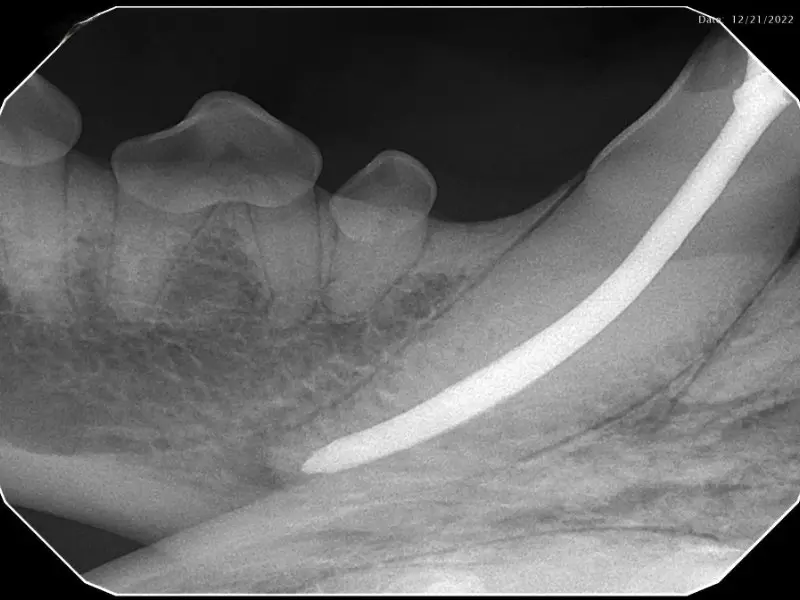

In simplified terms, root canal therapy is removal of the pulp (blood and nerve supply inside the tooth) within the root canal and pulp chamber of a tooth. The canals are then sterilized, filled, and sealed to prevent bacteria from creating infection. The main advantage of root canal therapy is maintenance of the tooth’s form and function. Also, it is usually less invasive than extraction. After treatment the tooth is no longer alive, but all of the structures supporting the tooth are still alive. In some cases, placement of a metal crown is advised to protect the tooth from further injury.

In pets, just like people, a small percentage of treated teeth may fail and require repeat treatment or extraction. Many cats and dogs do not tell us there are problems, thus regular rechecks under anesthesia are recommended to monitor the success of therapy.